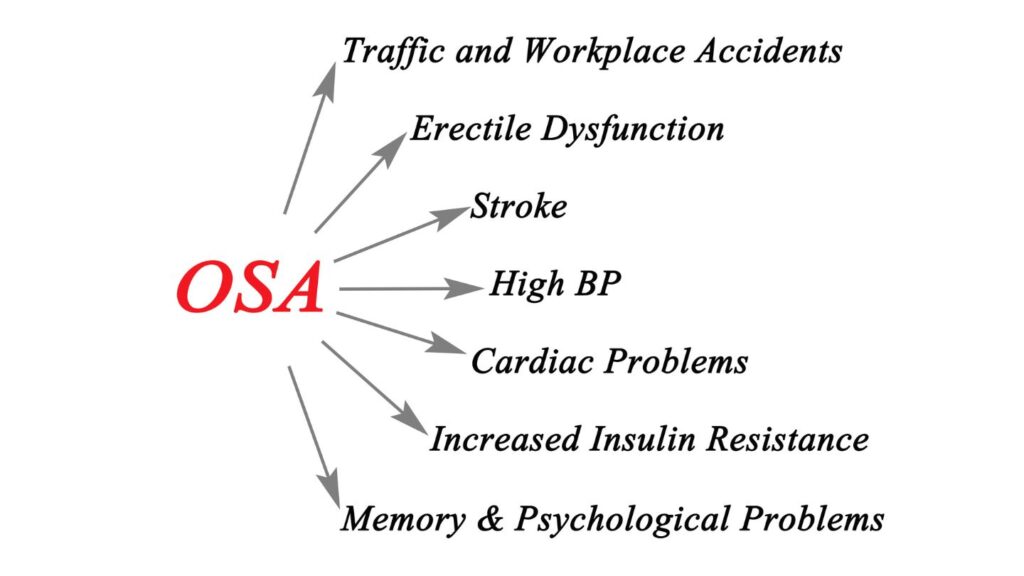

Obstructive sleep apnea (OSA) is a common sleep disorder where breathing repeatedly stops and starts during sleep due to the relaxation of throat muscles blocking the airway. This disrupts sleep, leading to excessive daytime sleepiness, snoring, and potentially serious health issues like heart problems, high blood pressure, stroke, and type 2 diabetes.

obstructive sleep Apnea - Complications